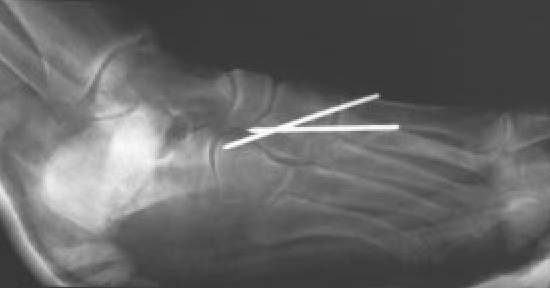

Fig. 5C.: Proyección lateral del mismo caso